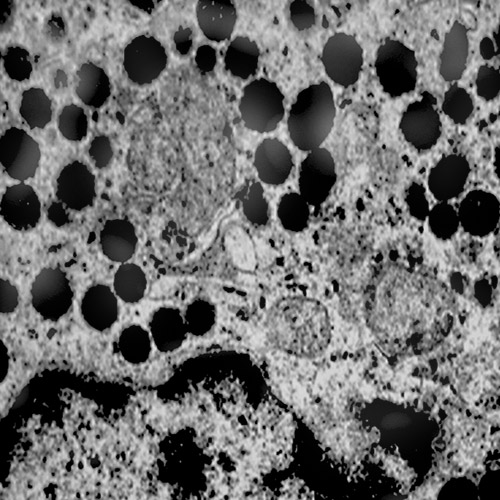

MICROAUTOFAGIA

I focolai di microautofagia si ritrovano frequentemente commisti a mitocondri disfunzionali e a reticolo- endoplasmatico in stato di stress.

Essi sono di piccole dimensioni, appaiono come vescicole, delimitate da una membrana a doppio strato, immerse nel citosol e

ricolme di materiale amorfo oppure di materiale amorfo commisto a frammenti filamentosi.

Fig.5  Fig.5a

Fig.5a